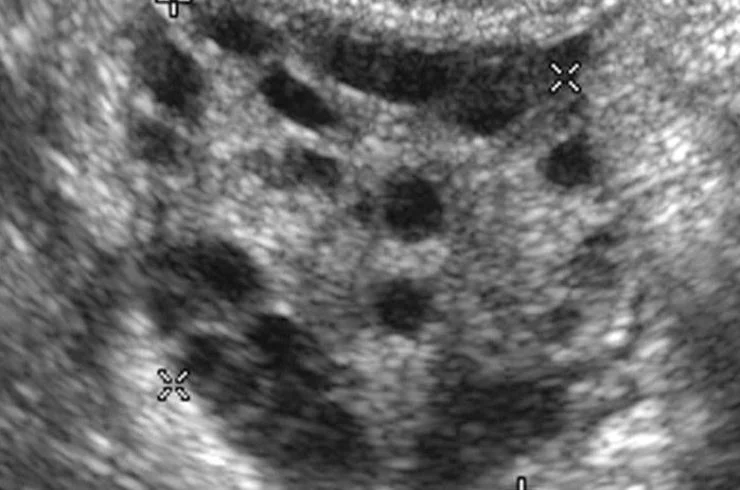

Antral Follicle Count

Antral Follicle Count (AFC) is a test that assesses the number of follicles in the ovaries, helping evaluate ovarian reserve, fertility potential, and overall reproductive health for women.